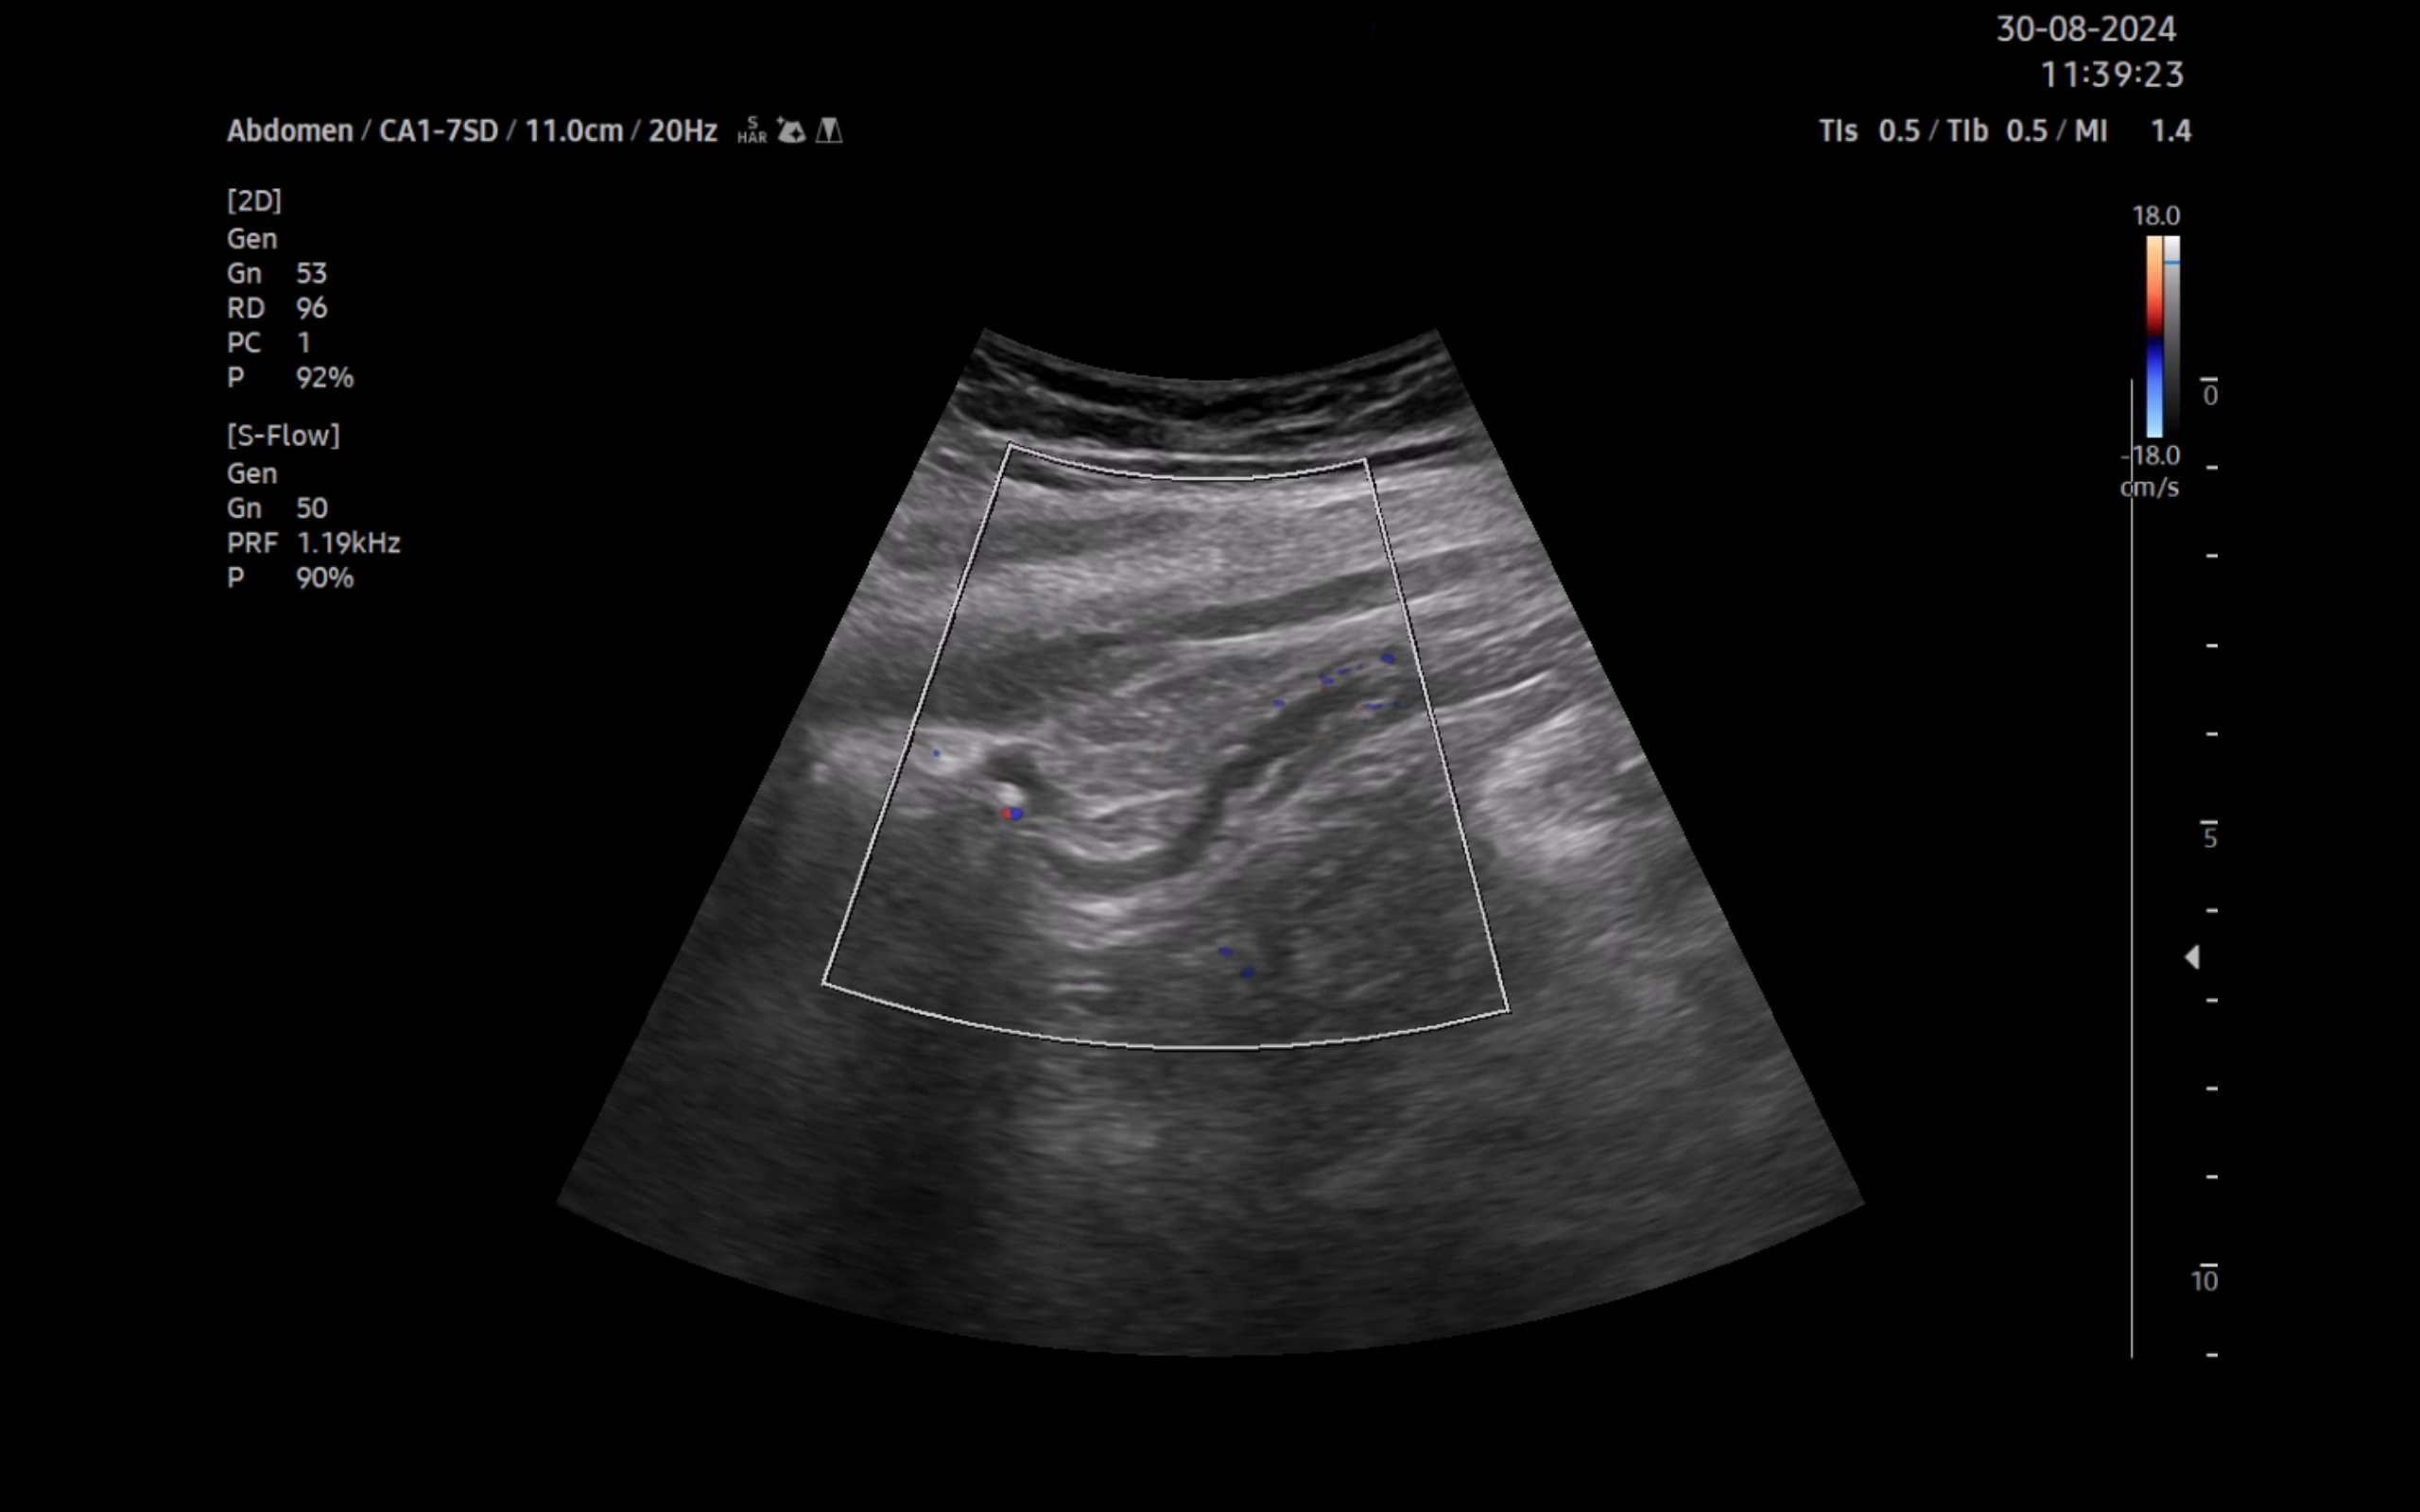

Ecografía clínica:

Imagen hiperecogénica con sombra en interior de vesícula biliar, hígado, páncreas, bazo y riñones sin alteraciones, vejiga orina poco replecionada. Llama la atención mínima imagen anecogénica en fondo de saco de Douglas. Apéndice visible en fid con diámetro 1,07 cm con captación aumentada con apendicolito con fenómeno centelleo.